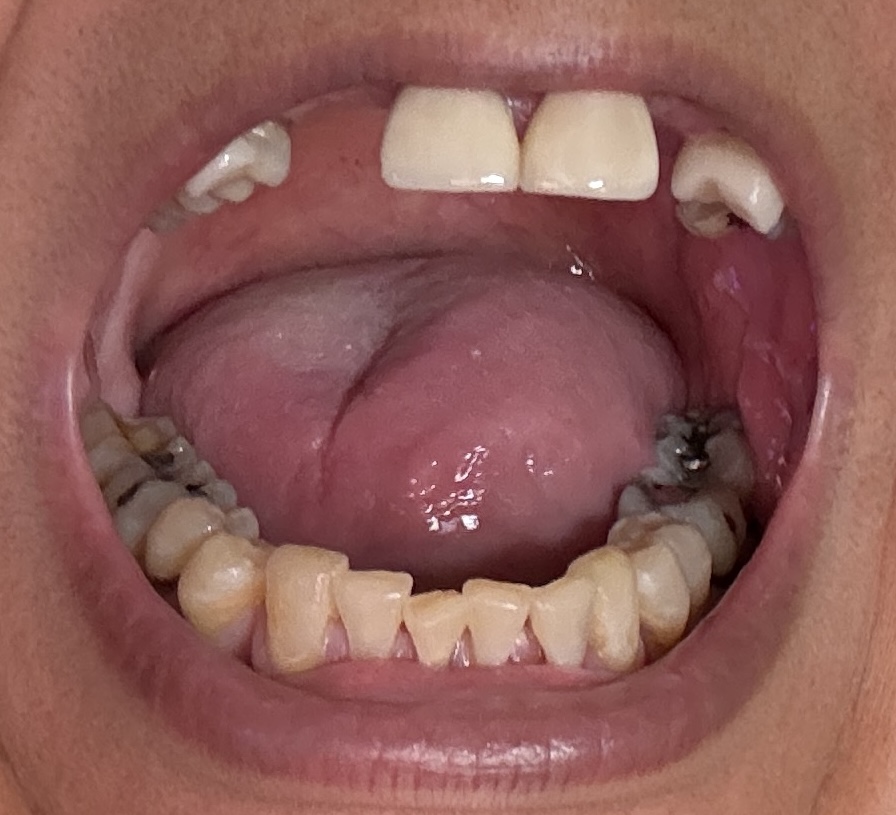

Dental Auction No. 11561: Several extractions and All-on-4 Top and bottom arches

Overall information (upper arch)

12,13,14 have had root canals in past and now have quite a bit movement. 2-5 have all had root canals in past and now the crowns are breaking down.

Overall information (lower arch)

Overall, all of my gums have receded and most of the bottom teeth are exposed w/ some roots and there are many cavities.